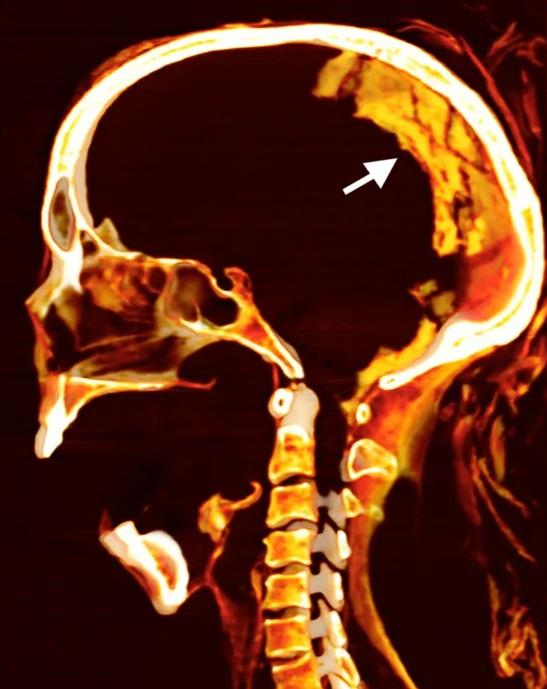

科學家藉由電腦斷層掃描(CT scan)對「尖叫女子」木乃伊進行虛擬解剖後推測,她可能在極度痛苦中離世,並在死亡時經歷一種罕見的肌肉僵硬,稱為「屍體痙攣」(cadaveric spasm)。

領導研究的埃及開羅大學放射學教授薩利姆(Sahar Saleem)解釋,屍體痙攣會在身體或精神承受劇烈痛苦後發生,收縮的肌肉在死後立刻變得僵硬。研究發現,「尖叫女子」過世時年約48歲,患輕度脊椎關節炎,已失掉部分牙齒。遺體大約在3,500年前經過防腐處理,那時是古埃及「新王國時期」(New Kingdom)。

薩利姆表示,木乃伊保存狀況良好,採用罕見且昂貴的防腐材料,再加上應用穿戴假髮、放置戒指等殯葬技術,似乎能排除人們進行防腐處理時出現疏漏,忘記合上她的嘴巴。

薩利姆指,如果當時負責殯葬的人沒有粗疏大意,便可以有其他解釋,例如「女子死時因極度痛苦而放聲尖叫,由於屍體痙攣,她的臉部肌肉收縮並保持這個模樣」。但他強調,女子的死因仍是個謎,無法確定甚麼原因讓她露出尖叫表情。